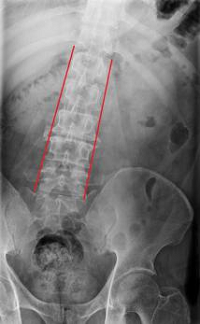

(一)、重度脊柱側(cè)彎畸形矯正

脊柱側(cè)凸、后凸及側(cè)后凸畸形不僅嚴(yán)重影響外觀,且可導(dǎo)致心肺功能障礙、脊髓壓迫引起的四肢無力、癱瘓等嚴(yán)重后果,但脊柱畸形矯正手術(shù)難度大、風(fēng)險高。我院脊柱外科團(tuán)隊專家在美國頂尖的脊柱畸形矯正中心經(jīng)過系統(tǒng)學(xué)習(xí)交流,結(jié)合3D打印技術(shù),開展了一系列高精尖矯形手術(shù),積累了豐富的手術(shù)經(jīng)驗和技巧,且均獲得滿意的臨床效果。